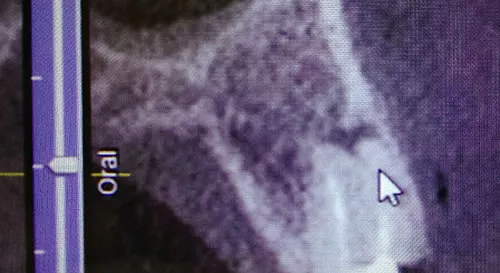

Warum reicht ein 2D-Röntgen manchmal nicht aus?

Oft klagen Patient:innen über Zahnschmerzen, doch auf einem herkömmlichen zweidimensionalen Röntgenbild (Einzelbild oder Panoramaaufnahme) ist keine eindeutige Ursache erkennbar. Das liegt nicht an einem Diagnosefehler des Zahnarztes – sondern daran, dass räumliche Tiefe (die 3. Dimension) auf solchen Bildern nicht darstellbar ist.

Beispiel:

Ein Zahn scheint auf dem 2D-Bild unauffällig. Doch das 3D-Röntgen (DVT) zeigt, dass eine der Wurzeln sich in einem knochenfreien Bereich befindet – ein eindeutiger Hinweis auf Entzündung oder Knochenabbau.

Zweidimensionales Röntgenbild der Zähne – Limitierungen der 2D-Röntgendiagnostik erklärt in der ACC Zahnklinik Basel

3D-Röntgen (DVT) für präzise Zahn- und Kieferdiagnostik – moderne Bildgebung in der ACC Zahnklinik Basel

3D-Röntgendiagnostik mit DVT – exakte Einblicke in den Kiefer

Das digitale Volumentomogramm (DVT) ermöglicht eine dreidimensionale Darstellung des Kiefers. Damit erkennt man:

• Welche Wurzel betroffen ist (buccal oder palatinal)

• Das genaue Ausmass von Knochenabbau

• Entzündungsherde, die im 2D-Bild unsichtbar bleiben

• Anatomische Strukturen für präzise Implantatplanung